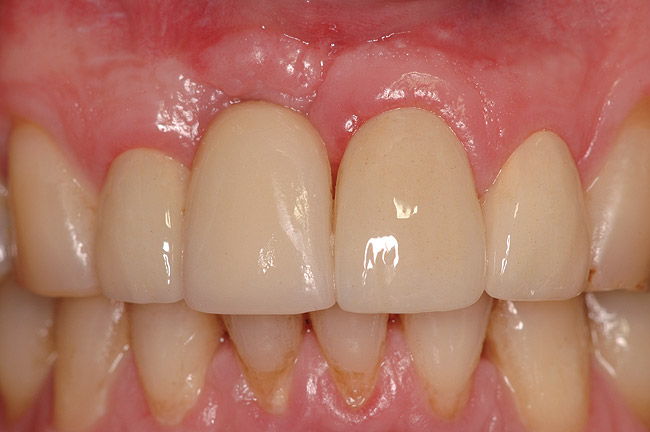

Figure 12  The healing healthy soft tissue 7 years post-sugery.

Figure 12

A 46-year-old man with an unremarkable medical history was referred for evaluation and treatment of the maxillary right central incisor implant. The implant, which had been placed 6 years prior, had never caused any problems until recently, when the patient noted both swelling and soreness at the site. Following 10 days of amoxicillin 500 mg tid, purulence was still present upon palpation of the tissue, and the patient was referred for consultation (Figure 6). Probing attachment loss of 10 mm on the distal aspect and 5 mm on the mesial were measured around the implant. Bone loss was advanced on the periapical radiograph at both the mesial and distal aspects of the hydroxyapatite-coated implant (Figure 7). Full-thickness facial and lingual flaps were reflected to access the implant and surrounding bone, with care taken to preserve the papilla. The defects around the implant on the mesial and distal were 1-wall, and bone loss was present on the direct facial and palatal aspects as well (Figure 8). The surface of the implant was decontaminated, followed by application of enamel matrix derivative. The lesion was filled with freeze-dried bone allograft (Figure 9). The graft-biologic was covered by a flowable polymer barrier (Figure 10). The flaps were coronally advanced and secured with monofilament sutures (Figure 11). The patient was prescribed amoxicillin with clavulanic acid and an oral rinse of 0.12% chlorhexidine during the post-operative period. The healing progressed uneventfully, achieving both a favorable soft-tissue profile and substantial bone fill, as determined radiographically. These results were stable for 7 years (Figure 12 and Figure 13).